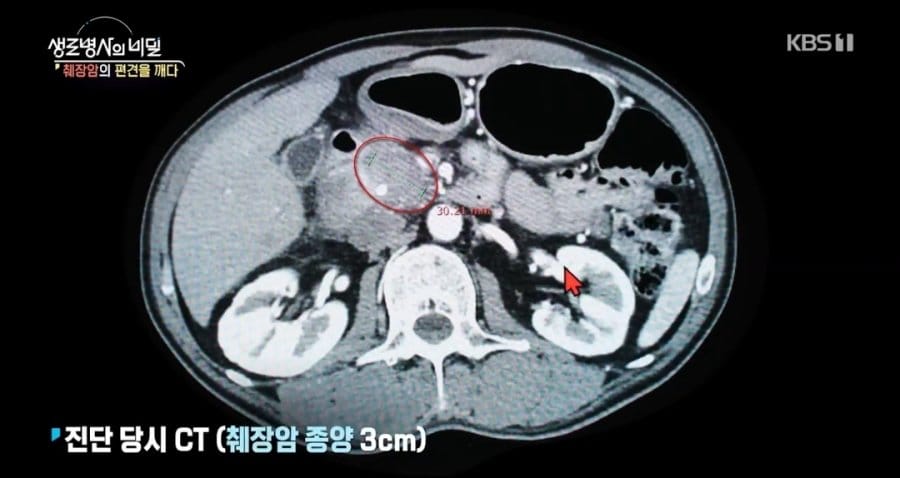

췌장암 3기 판정받은 사람이 느낀 증상 차례 숨기기 췌장암 3기 판정받은 사람이 느낀 증상 관련 암이 의심되는 신호암 직간접적으로 겪은 사람들이 말하는 전조증상(간호연구) 역사 근거기반간호(간호연구) 정의 목적 필요성 양적연구 질적연구최근 확산중인 “중국발 미스테리 눈병” (잠적 폐사 노다 바이러스)의사가 이상한 엄마라고 해서 속상한 사람햇빛에 변해가는 얼굴 결국 시력까지 잃었습니다 (색소성 건피증 – 자외선 면역 질환) Post Views: 438관련태그:췌장암췌장암 3기췌장암 3기 판정받은 사람이 느낀 증상췌장암 증상이전세상에서 제일 비싼 약 졸겐스마 (척수성 근위축증 SMA)다음(건강사정) 통증 사정